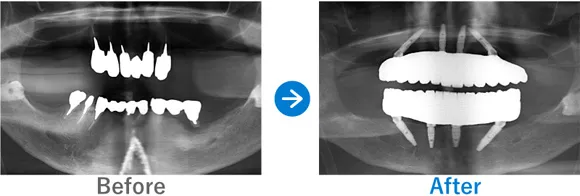

Case1

歯が1本もない状態からインプラント治療で噛める幸せを取り戻された方

歯が1本もない状態、10年以上前から上下総義歯(総入れ歯)

上顎ALLON6、下顎ALLON4、

リオペ上顎追加埋入ザイゴマインプラント2本

9,823,000円(上顎6,248,000円、下顎3,575,000円/内訳:上顎オールオン6(ノーベルザイゴマインプラント2本・ストローマンインプラント4本)、下顎オールオン4(ストローマンインプラント4本)3Dモデルガイド*、仮歯、セデーション、ボツリヌストキシン注射、3D模型、保証10年)

来院の背景

10年以上前から上下義歯(総入れ歯)だが、義歯が痛くて、食事に困っている。他院にて仮義歯を作ってもらっていたが担当医が辞めたこともあり、インプラントを検討。ネットで探して退院。痛みなく食事がしたい。

治療結果

上下ALLON4、右上5、左上3、リオペザイゴマインプラント2本追加順調の経過、治療終了、メンテナンス来院。インプラントで噛めるようになり、喜んでいただいた。しっかりセルフケアを頑張っておられます。お顔の表情も明るくなられて、気持ちも前向きに過ごされています。